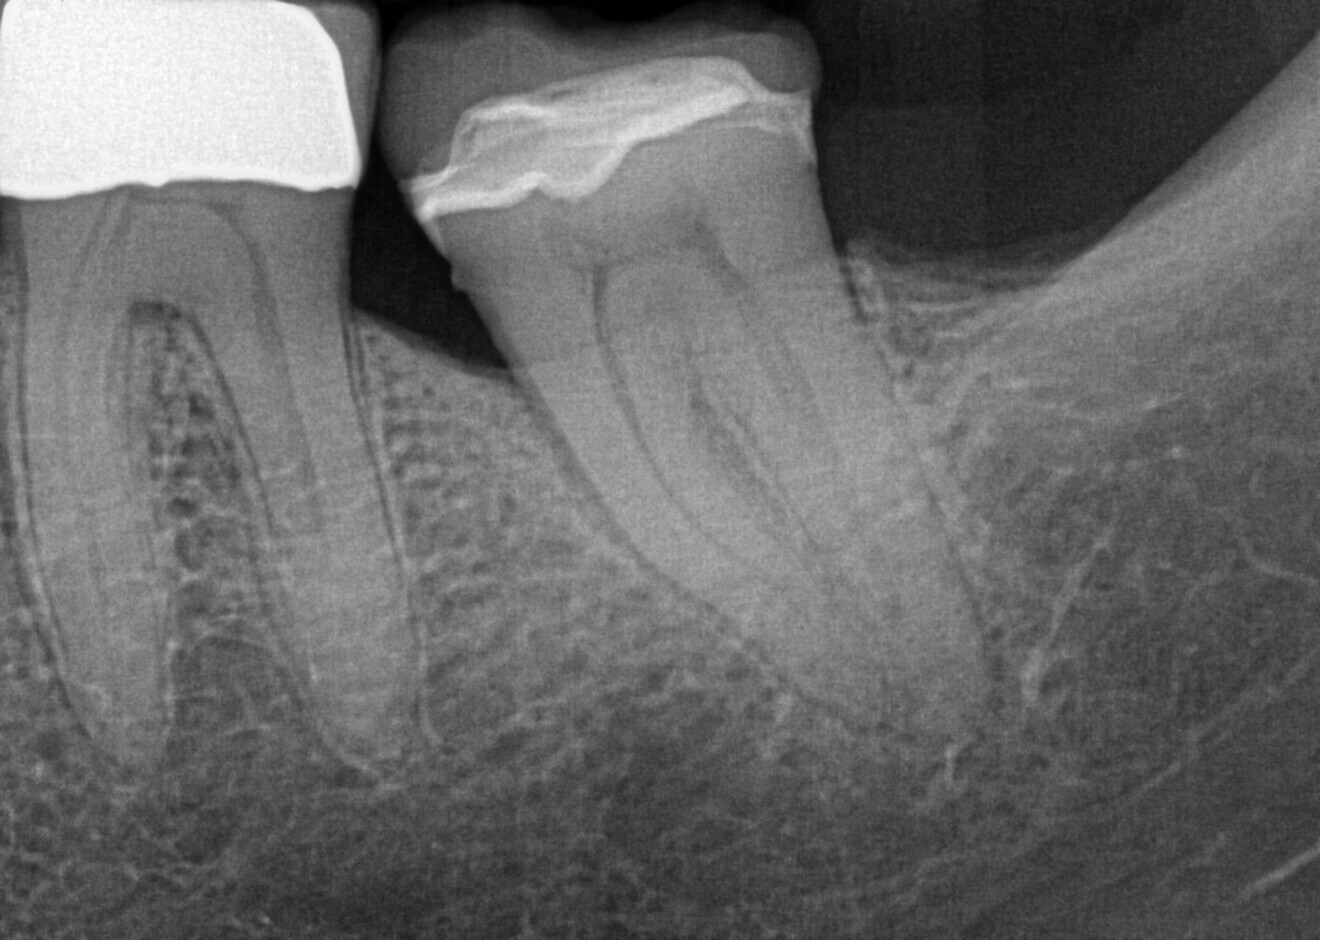

The pre-op radiograph shows tooth #37, which had been treated with a ceramic restoration two years earlier after removal of deep caries, diagnosed with irreversible pulpitis and periapical periodontitis. (Image: Dr Sabine Remensberger)